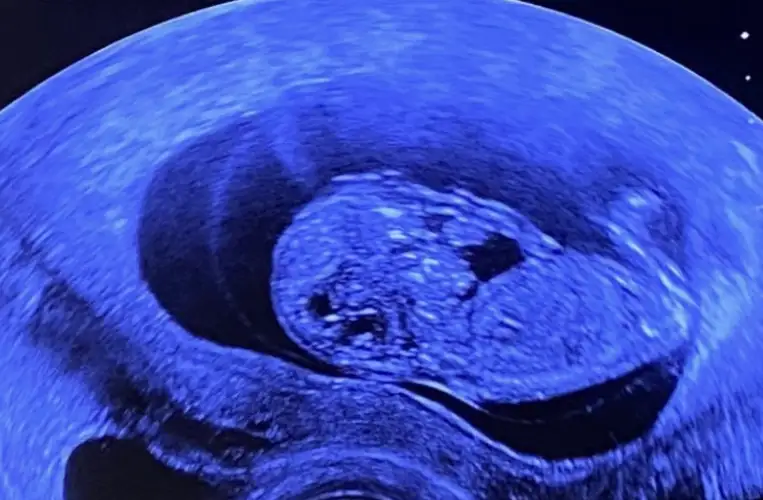

Sevgili @ıkrameyra cinsiyet tahmini alabilir miyim 🌹💕

BDA5C7BD-3496-4BB1-A970-938708FDFC4E.jpeg

Eklentiler

• 61A9F4EF-9683-43B4-B5BD-00CCB355CF56.webp

61A9F4EF-9683-43B4-B5BD-00CCB355CF56.webp

28,5 KB · Görüntüleme: 40